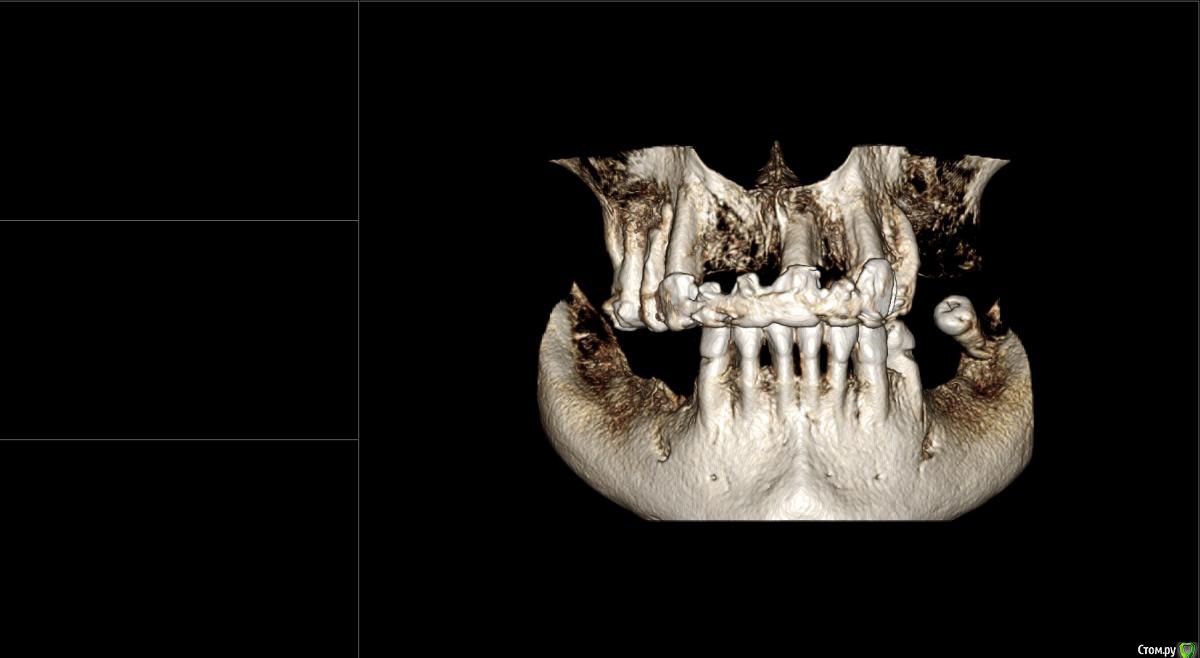

kamranchick Опубликовано 17 февраля, 2015 Поделиться Опубликовано 17 февраля, 2015 Добрый вечер.Имеется следующая проблемаПациент обратлся с жалобами в области отсутствия жевательных зубов, планируется имплантация.Вопросы такого плана, в области 3 сегмента думаю сделать расщепление гребня, установка имплантов 3,75/8 и аугментация костью Ostebiol Gen-Os, мембрана.В области 4 сегмента больше сомнения, планируется титановая сетка +аугментация, либо расщепление опять же, планирую разделить восстановление и имплантауию на 2 этапа в 4 сегментеКакие будут комментарии? Ссылка на комментарий

Shuvalov Опубликовано 17 марта, 2015 Поделиться Опубликовано 17 марта, 2015 Добрый вечер.Имеется следующая проблемаПациент обратлся с жалобами в области отсутствия жевательных зубов, планируется имплантация.Вопросы такого плана, в области 3 сегмента думаю сделать расщепление гребня, установка имплантов 3,75/8 и аугментация костью Ostebiol Gen-Os, мембрана.В области 4 сегмента больше сомнения, планируется титановая сетка +аугментация, либо расщепление опять же, планирую разделить восстановление и имплантауию на 2 этапа в 4 сегментеКакие будут комментарии?Думаю Mane прав И получите прогнозируемый результат! Без сетки! Сосиска рулит Ссылка на комментарий